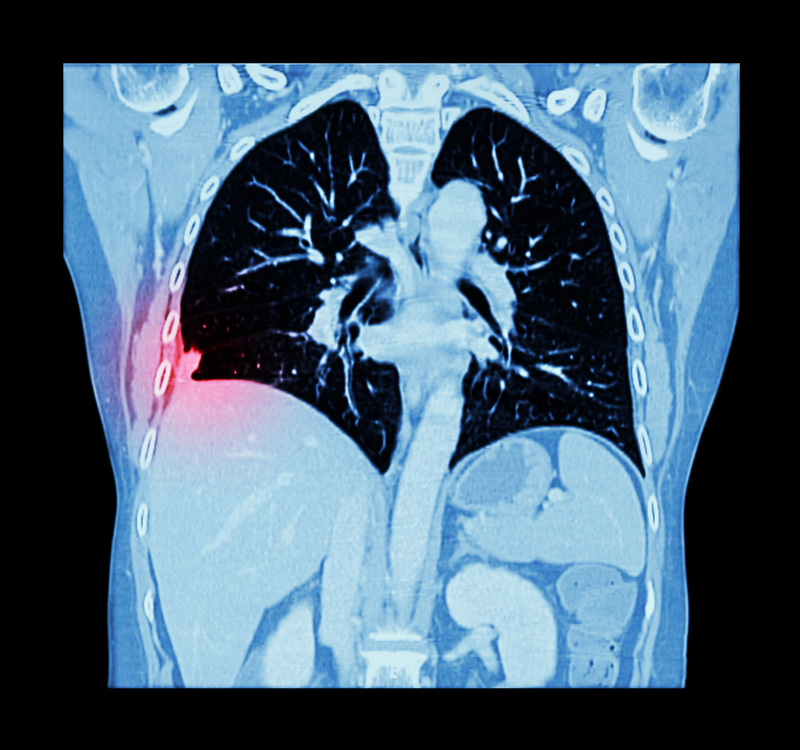

Researchers from University of Central Florida in the US have taught a computer how to detect tiny specks of lung cancer in computed tomography (CT) scans, which radiologists often have a difficult time identifying.

The Artificial Intelligence (AI) system is about 95 per cent accurate, compared to 65 per cent when done by human eyes, the team said. "We used the brain as a model to create our system," one of the researchers Rodney LaLonde said in a statement released by the university.

The approach is similar to the algorithms that facial-recognition software uses. It scans thousands of faces looking for a particular pattern to find its match. The group fed more than 1,000 CT scans into the software they developed to help the computer learn to look for the tumours, according to the research to be presented at the MICCAI 2018 conference in Spain in September. "I believe this will have a very big impact," said Assistant Professor Ulas Bagci.

"Lung cancer is the number one cancer killer in the US and if detected in late stages, the survival rate is only 17 percent. By finding ways to help identify earlier, I think we can help increase survival rates," Bagci added. The next step is to move the research project into a hospital setting. After that, the technology could be a year or two away from the marketplace, Bagci said.